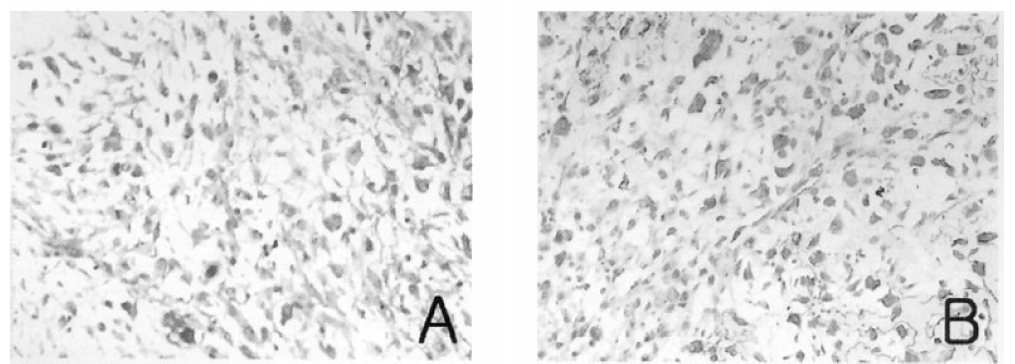

To define the exact etiology of the radiologic findings, thoracoscopic wedge biopsy of the left lower lobe demonstrated the mass to be contained within the lateral basal segment and the medial basal segment of the left lower lobe. On gross section, the mass was 10×9×7 cm in size, sharply circumscribed and smoothly contoured. It had no involvement to the chest wall and no endobronchial component, but extended centrally to hilar areas. Light microscopic examination demonstrated a tumor composed of malignant epithelial components and mesenchymal components. The carcinomatous components consisted of poorly differentiated squamous cell carcinoma and the sarcomatous components were considered chondroid sarcoma in the light of microscopic findings (Figure 3). Light microscopic immunohistochemical analysis showed that the tumor cells in the carcinomatous component reacted with anti-epithelial membrane antigen (EMA) antibody and the tumor cells in the sarcomatous component reacted with anti-vimentin antibody (Figure 4). He underwent workup for distant metastasis, the findings of which were unremarkable. Therefore, left lower lobectomy was performed with lymph node dissection. There was no microscopic evidence of lymph node metastases making this the international TNM stage lb (T2N0M0) lesion.

Figure 3.

Microscopic views. The epithelial component shows poorly differentiated squamous cell carcinoma (A) and the mesenchymal component shows chondrosarcoma (B). (H & E stain, × 400)